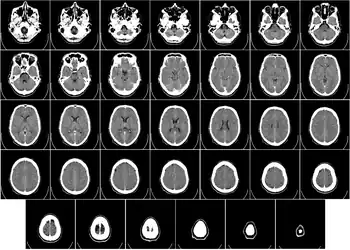

- Del Proyecto "Humano Visible" (Visible Human Project de la Biblioteca Nacional de Medicina de Estados Unidos. En este proyecto, dos cadáveres humanos (de un hombre y una mujer) fueron congelados y luego cortados en láminas delgadas, que fueron fotografiadas y digitalizadas individualmente. Esta sección está tomada a una pequeña distancia de la parte superior del cerebro, y muestra la corteza cerebral (la capa celular plegada al exterior) y la sustancia blanca subyacente, que consiste en tramos de fibra mielinizada que viaja hacia y desde la corteza cerebral.